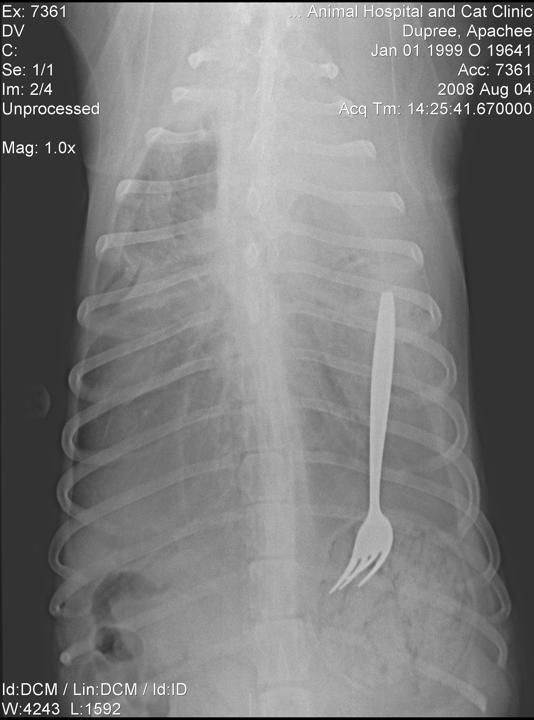

Apache, un Husky de 10 años, al parecer tenía mucha hambre y no solo acabó con su comida, sino con un tenedor que estaba en el recipiente. Fue atendido en enero del 99 en el Veterinary Specialty Hospital of the Carolinas. Splash News